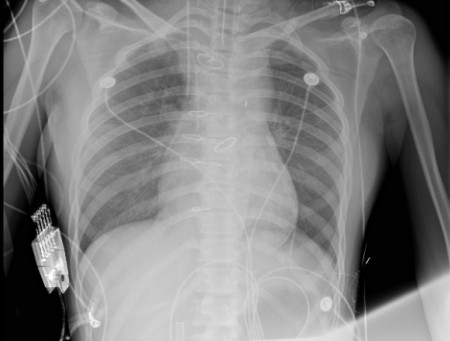

1 资料与方法患者女性,19岁,因“突发胸痛14 h”入院。患者14 h前无明显诱因出现胸骨后疼痛,呈紧缩感,伴有胸闷、呼吸困难,间断咳嗽。近期有听力下降、腹泻病史。8 h前就诊于外院时查体:体温测不出,Bp 53/36 mmHg(1 mmHg=0.133 kPa),呼吸40次/min, 脉搏137次/min,SPO2 93%,神志淡漠,全身皮肤湿冷,黏膜无黄染及出血点,颈静脉无怒张。听诊双肺呼吸音粗,可闻及满肺湿啰音,心音不清,腹部查体无异常,双下肢足背动脉搏动对称。化验结果提示WBC 29.3×109/L,NE 85.4%,TnT 93 ng/L,pro-BNP 2 047 pg/mL,PCT 0.11 ng/mL, 血气分析:pH 7.349,PCO2 31.2mmHg,PO2 67.2 mmHg,HCO3- 17.2 mmol/L,Lac 5.7 mmol/L。心电图提示:窦性心动过速、AVR导联ST段抬高,余导联ST段压低;床旁心脏超声提示EF 52%,二尖瓣中度返流、三尖瓣中重度返流,未见室壁节段性运动性异常。考虑心源性休克,原因尚不明确,给予机械通气、血管活性药物、补液等抗休克治疗,同时联系本院急诊ECMO团队,本院急诊ECMO团队到达现场后,患者突然出现室颤,给予胸外按压及电除颤后逐渐恢复窦律,立即进行V-A ECMO上机指征及预后评分SAVE评分评估,符合V-A ECMO上机适应证,约30 min成功上机运转,流量3.5 L/min,复查外周动脉血气分析: pH 7.305,PCO2 21 mmHg,PO2 73.4 mmHg,HCO3- 10.5 mmol/L,Lac 8.4 mmol/L。后转运至本院急诊病房,转运途中行生命体征、血气分析、ACT等常规监测,至病房后患者ECMO支持下血压仍需大剂量血管活性药物维持且脉压差较小,观察ECMO动静脉管路颜色极为接近,床旁经胸心脏超声提示主动脉瓣重度返流,为明确原因立即行急诊CT检查及床旁经食道超声心动图检查。本院肺CT(图 1)提示肺水肿,床旁经胸心脏超声提示主动脉瓣大量返流但心室收缩可,请超声影像科进一步行床旁经食道超声检查提示无冠窦呈瘤样凸向右房侧,瘤壁上可见宽约0.6 cm破口;主动脉瓣舒张期无冠瓣脱向左室流出道侧(图 2、图 3)。立即请心血管外科会诊,急诊行主动脉瓣机械瓣膜置换术+主动脉窦修补术+房间隔造口术+主动脉球囊反搏置入术+心脏起搏器置入术,术中探查与经食道超声所见相符(图 4、图 5),考虑左心功能差,左心压力较高,行房间隔造口术。术后复查胸片肺水肿基本消失(图 6),继续呼吸机与ECMO支持,因患者肺功能良好,自主呼吸良好,为减少呼吸机相关肺损伤、呼吸机相关肺炎等发生,术后第4天神志清醒后拔除气管插管,机械通气减轻左心前后负荷的作用去除后,继续ECMO与IABP支持,ECMO增加左心后负荷时IABP可降低左室后负荷,达到左心减压的目的,术后第10天心功能恢复,下调ECMO流量后循环可维持,予以撤离ECMO,术后第12天撤离IABP,后停用肝素持续泵入抗凝,达肝素皮下注射联用华法林口服抗凝3 d后,单用华法林口服抗凝,维持INR达标,在康复期间患者活动时左下肢疼痛,左侧足背动脉搏动减弱,下肢动静脉超声提示左侧股浅动脉血栓形成,期间增加华法林剂量后血栓未见明显变化,后行下肢股浅动脉切开取栓术,术后33 d患者完全康复顺利出院。

| 图 2 经食道超声心动图 |

主动脉根部造影为诊断主动脉窦瘤的“金标准”[10], 但本例患者生命体征不稳定,外出检查需携带呼吸机及ECMO机器,转运风险较大,因此采用床旁心脏超声检查是非有创检查的最佳手段之一。本案例外院经胸心脏超声提示三尖瓣中重度返流,入院后床旁经胸心脏超声仅发现主动脉瓣重度返流,仍无法明确心源性休克原因,联系超声影像科通过经食道超声心动图发现无冠窦瘤破裂入右心房才最终明确诊断。主动脉窦瘤的诊断需要技术高超且临床经验丰富的超声科医生,也反映出急诊科医生需学习掌握经食道超声心动图技术。